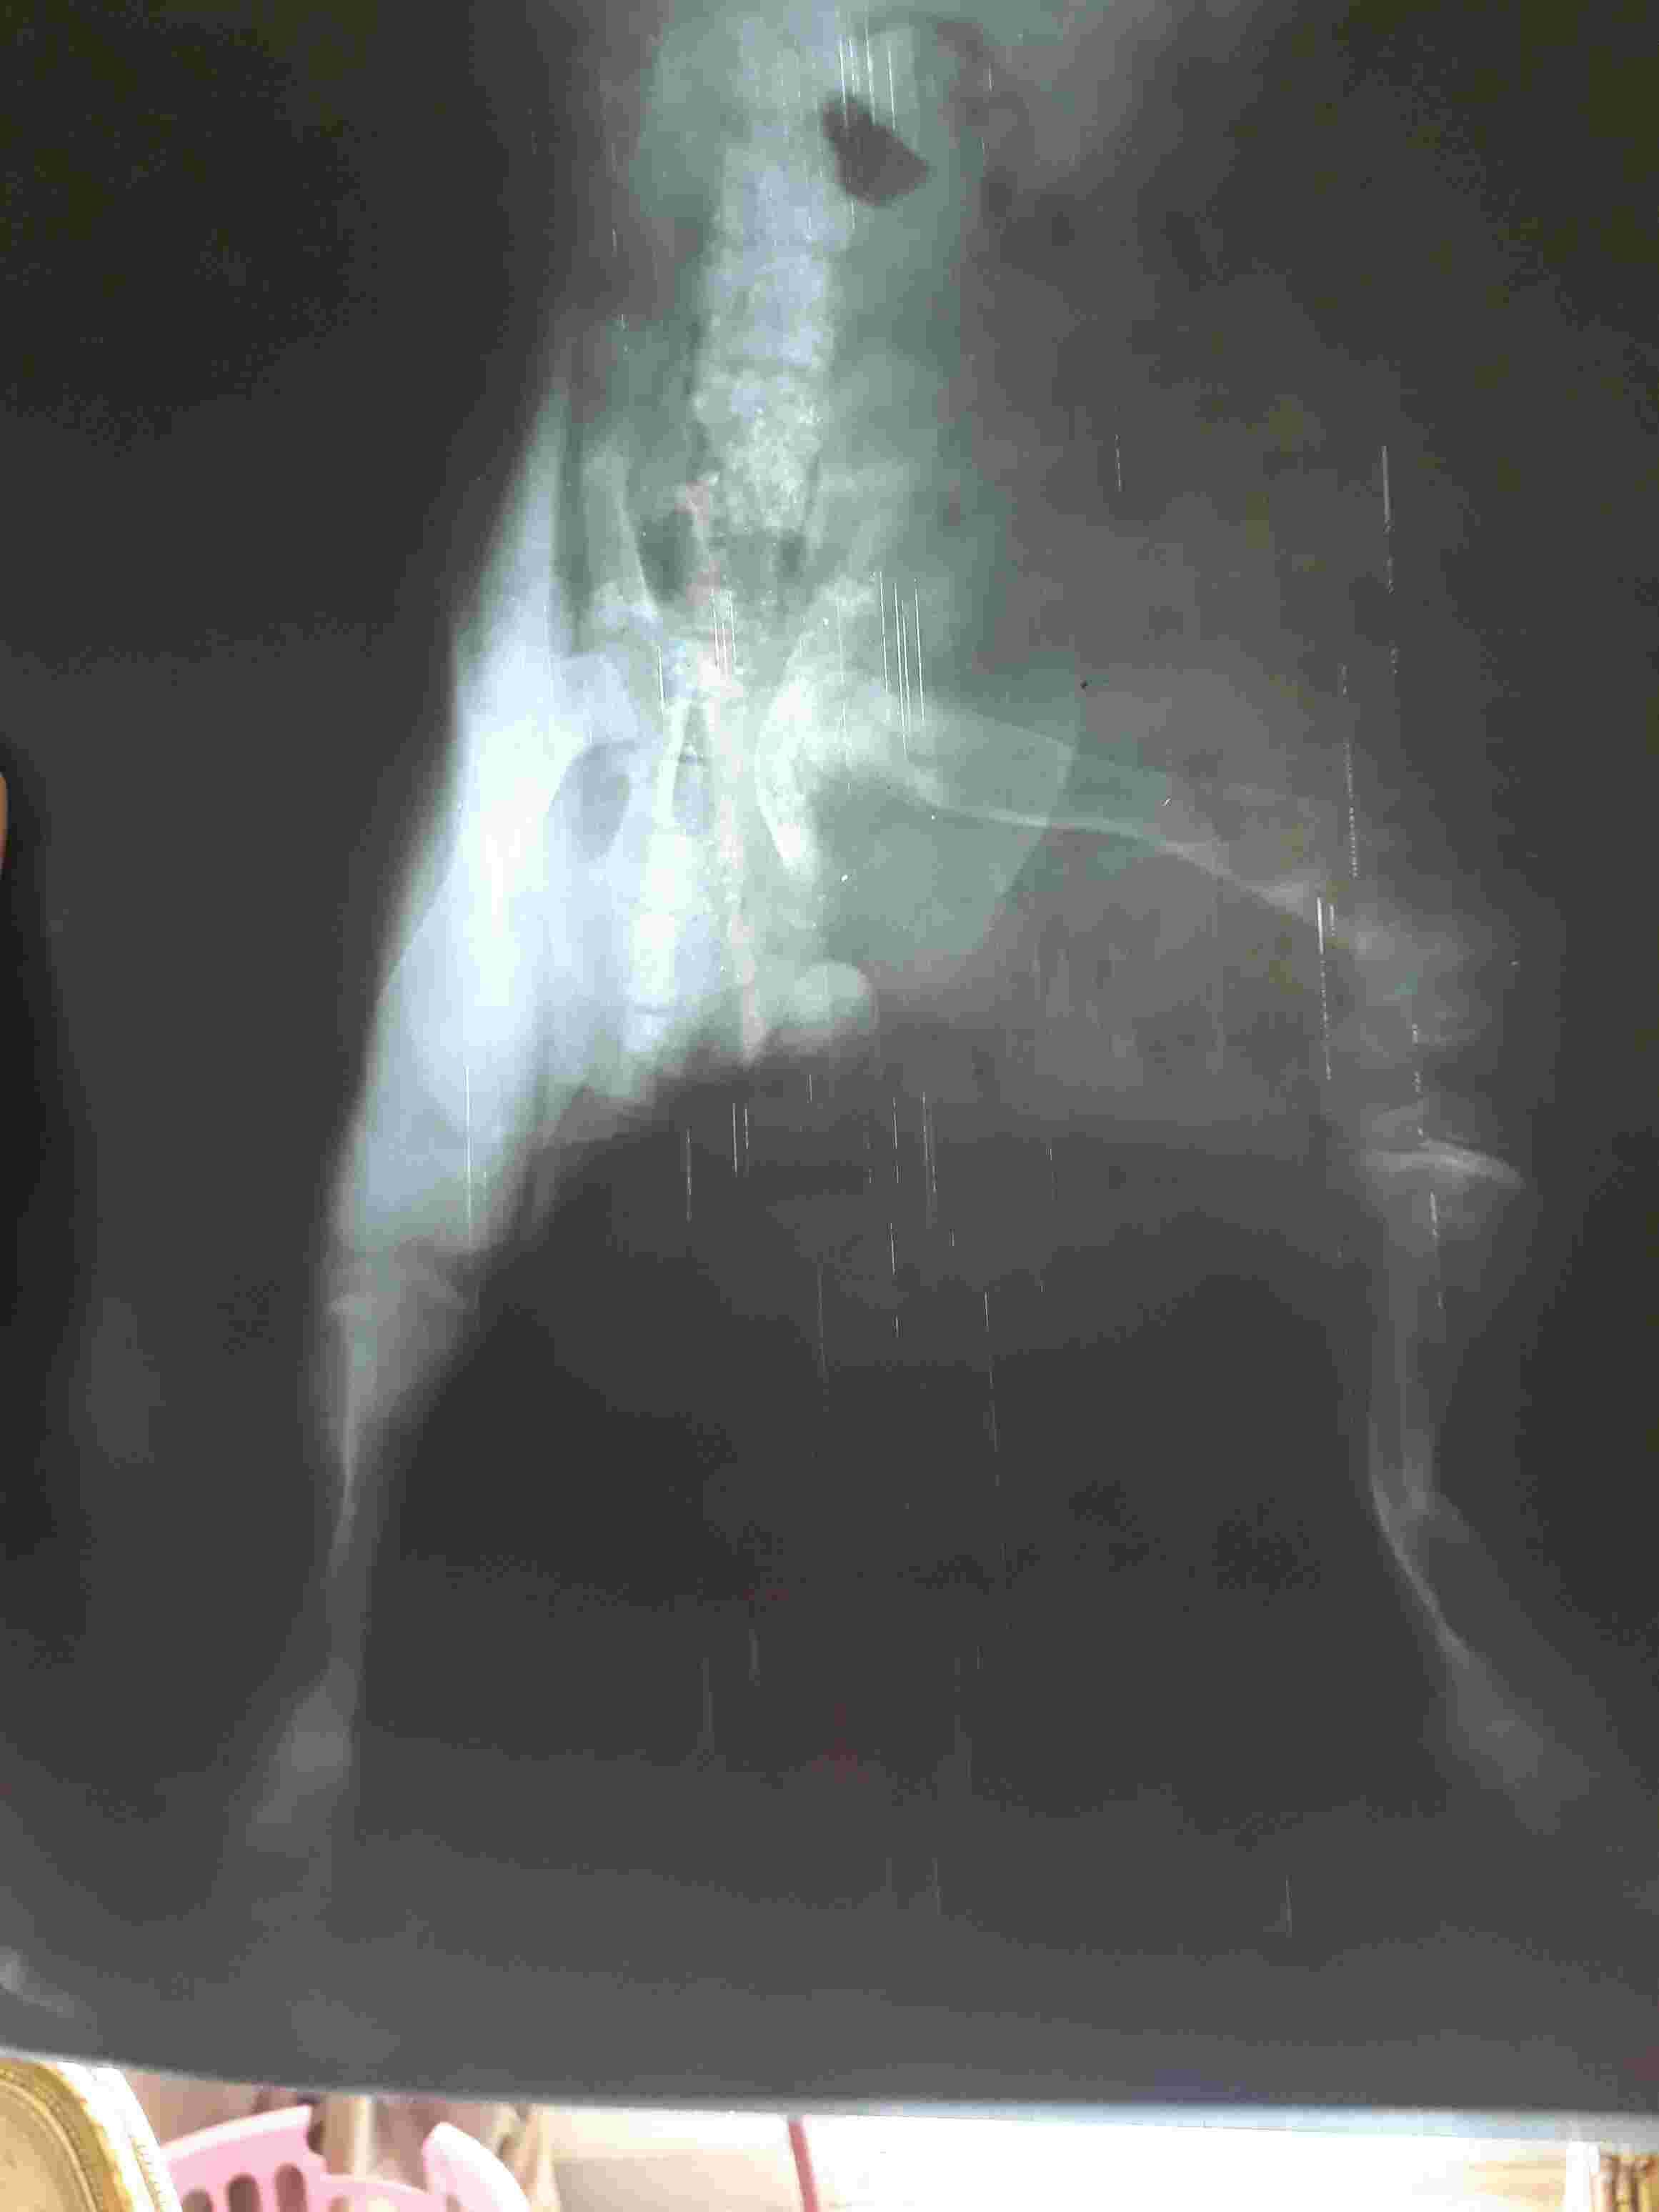

My dog fell on her leg 3 weeks ago. She has been checked by 2 vets and said not broken. They prescibed jel for inflamations and painkillers. She also took shots and tablets of calcium/magnesium zinc and D3. She didnt get better. Took her to a 3rd vet today who confirmed leg is broken and bone is misfit. The vet put bandage on the leg and said if we notice swelling we take bandage off then re apply. I am attaching her xrays. Pls need your kind advise if this is correct.

The image quality makes it very difficult to see the images in the amount of detail needed to properly assess them, but it does appear that the bone was fractured and is healing. The bone appears to not be healing straight, likely because the leg was not splinted when the fracture first occurred. You should definitely continue to monitor the bandaged/splinted leg. If you notice that Dixie's toes are blue or are cold to the touch the bandage/splint needs to be removed immediately and re-wrapped. I would definitely having a veterinarian re-wrap the bandage/splint as there are special bandaging/splinting techniques and materials used to accomplish different things. Your veterinarian would be the best person to do this to ensure proper healing. I hope this helps and best of luck to both you and Dixie.

Poor Dixie! I'm sorry it's been such a struggle to get an answer! It's difficult to tell - the photos are a bit fuzzy, but I do think I'm seeing a mid-shaft left tibial fracture with some displacement. I wonder if she may have simply had a non-displaced hairline fracture initially that was difficult to see on x-rays, which could have been why the first two vets didn't see it. Hard to know without seeing the x-rays they saw (I assume these x-rays are from the 3rd vet). Fortunately, young pups like Dixie heal quickly, and very often do well with a good splinted bandage. I agree with your vet to watch for swelling (if they left the tips of her toes exposed you can watch for her toes to spread apart, which would indicate swelling) - however, I would hesitate to have you remove or re-apply the bandage on your own. It is worth having the vet do this, as doing it incorrectly could lead to serious problems. Too loose a bandage will not stabilize the broken leg appropriately, and too tight a bandage will cut off the blood supply. Better to have the vet do it! Hope Dixie feels better soon - happily young pups often can heal fractures within 6-8 weeks! Good luck! Hope this helps.